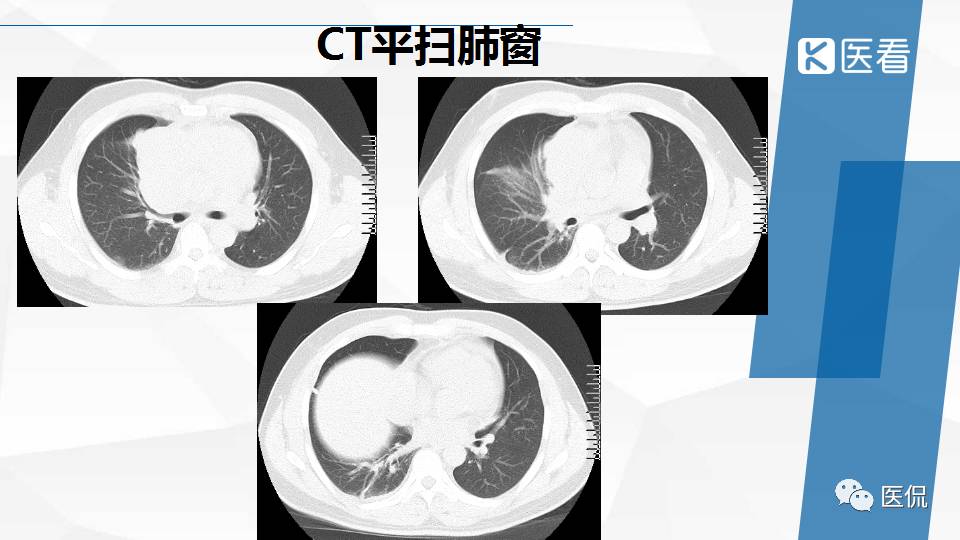

纵隔精原细胞瘤案例 (精原细胞瘤影像表现与鉴别诊断)

精原细胞瘤ct影像,精原细胞瘤影像特征